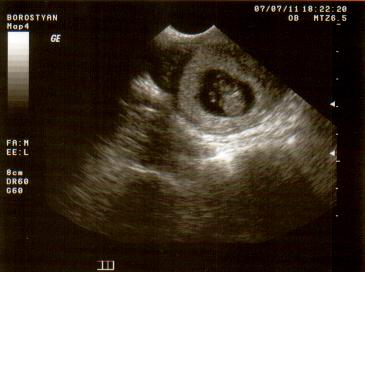

Négy órás kórház kálvária(kettőbe voltam-honvéd,szabolcs utcai)mert szervezetlenség van ézt a bőrömön tapasztaltam.Kihívta a férjem a mentőt,mert látszólag senkinek nem volt baja,leszámítva,hogy reszkettem mint a kocsonya,de aggódtunk a Bogyók miatt.Kemény volt a pocim,de szerintem a stressz miatt.Volt ctg,ultrahang,méhszájvizsg.ha valakit részletesebben érdekel,leírom.az elsőbe írtam,most nem akartam...

)csak egyszerűen hycomat,mert két gyerek nő a pocakomban.(hál' Istennek!